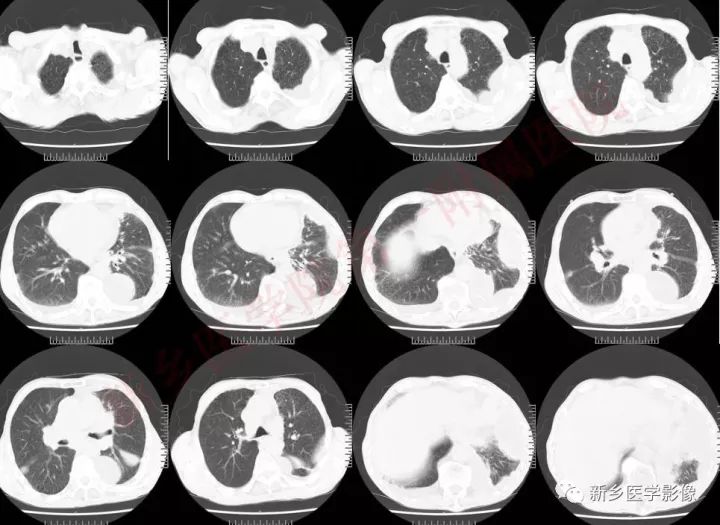

常规CT分型

把小细胞肺癌分为中央型和周围型,临床上根据病灶分布又将其分为局限期和广泛期。也有人依据现代CT的发展和治疗的需要将小细胞肺癌分为中央型、中央型合并纵膈型、周围型、周围型合并纵膈型、沿淋巴管扩散型、胸膜转移型、肺叶型及类肺炎型,共8型

1、病灶不累及粘膜,在粘膜下生长,包绕单个支气管形成明显的肿块,支气管变形,管腔通畅。CT表现为沿支气管分布的茄形或纺锤形肿块,受累支气管受压狭窄:

2、病灶累及粘膜表面、支气管管腔被包绕,并向腔内形成结节状肿物、突向管腔内CT表现为肿块向管腔内突破,引起阻塞性肺炎和不张,但出现较晚。

肿块形态及强化:

中央型小细胞肺癌主要起源于5级以上支气管,分叶少,边界较光滑,不易发生空洞,肿块一般沿支气管长轴蔓延,包绕支气管,增强后呈中度强化;周围型小细胞肺癌,肿块多呈结节状或葡萄状,结节状病灶多为单结节型,形态较规整,边缘较光滑,无分叶或浅分叶,毛刺征及胸膜凹陷出现率低;葡萄状病灶表现为沿小支气管生长的串珠状大小不等结节病灶,密度较均匀,少有空泡征、空气支气管征,增强后,出现轻中度强化。这主要与小细胞肺癌的病理形态有关,小细胞肺癌,癌细胞小而呈短梭形,胞浆少,癌细胞排列密集,因此形成的肿块密度较大,瘤体密实,内聚力强,纤维成分少,血供相对丰富,肿块各方向生长的速度也较均衡,使得小细胞肺癌肿块不容易形成较深的分叶和空洞。

胸腔积液与胸膜

小细胞肺癌沿淋巴管扩散的特点,容易造成小叶间隔线增厚、凸起,当侵及胸膜时,可引起胸膜多发结节影或磨玻璃影,伴有恶性胸腔积液。CT表现为胸膜面不规则增厚、凹凸不整的细小结节影及胸腔积液,增强可见增厚的胸膜及结节影轻至中度强化表现。按照美国退伍军人医院肺癌研究组分期系统标准,双侧胸腔积液发生时,病情已进展到广泛期,对于患者的治疗和预后将产生重要的影响